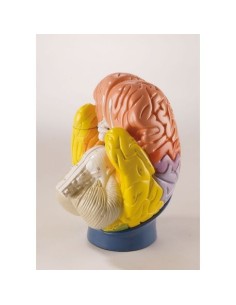

Scopri il Mondo dell’Anatomia con Modelli anatomici di Precisione

Benvenuto su Tuttoanatomia.it, il portale di riferimento in Italia per l’acquisto di modelli anatomici, poster, lettini portatili, simulatori medici e letteratura specialistica. Con i nostri modelli anatomici di 3B Scientific ed Erler Zimmer, leader mondiali nel settore, offriamo un’esperienza di apprendimento senza pari.

Modelli Anatomici Dettagliati per Ogni Necessità

Dal cranio in 22 parti con incastri magnetici ai modelli di colonna vertebrale, da quelli di articolazioni a quelli di cuore, ogni pezzo della nostra collezione è progettato per un’immersione totale nello studio dell’anatomia umana. I nostri modelli, realizzati tramite scansioni di ossa vere, garantiscono un’esperienza tattile autentica e una fedeltà di peso quasi identica agli originali.